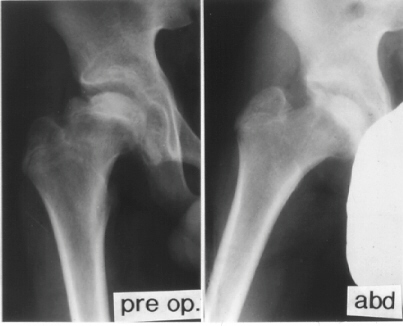

K.B.. 12-year-old boy. B.W. 63 kg(139 Ib.) . Perthes disease.

He had right hip pain and limping for seven weeks. When he was

first seen at University Hospital of Niigata, the right femoral

head was deformed already and collapsed slightly on X-ray.

The lateral part of the femoral head showed an impingement lesion.

Because good sphericity of the posterior part of the femoral head

was still preserved,

Sugioka's rotational osteotomy was advised. Pre-operative range

of motion was flex.90, abd.35, e.r. 40, and i.r. 15. The femoral

head was anteriorly rotated by 75 degrees and varus angulation

by 15 degrees was made.

- Anteroposterior and true lateral radiographs should be performed.

For the true lateral radiograph, the patient should be positioned

supine, with the hip in precisely 90 degrees of flexion and 45

degrees of abduction and with neutral rotation.

- The preoperative lateral view radiograph shows the A-P view

of the femoral head as it will appear after 90 degrees of posterior

rotation.

- In contrast, a preoperative lateral view in a reversed position

shows the A-P view after 90 degrees of anterior rotation.